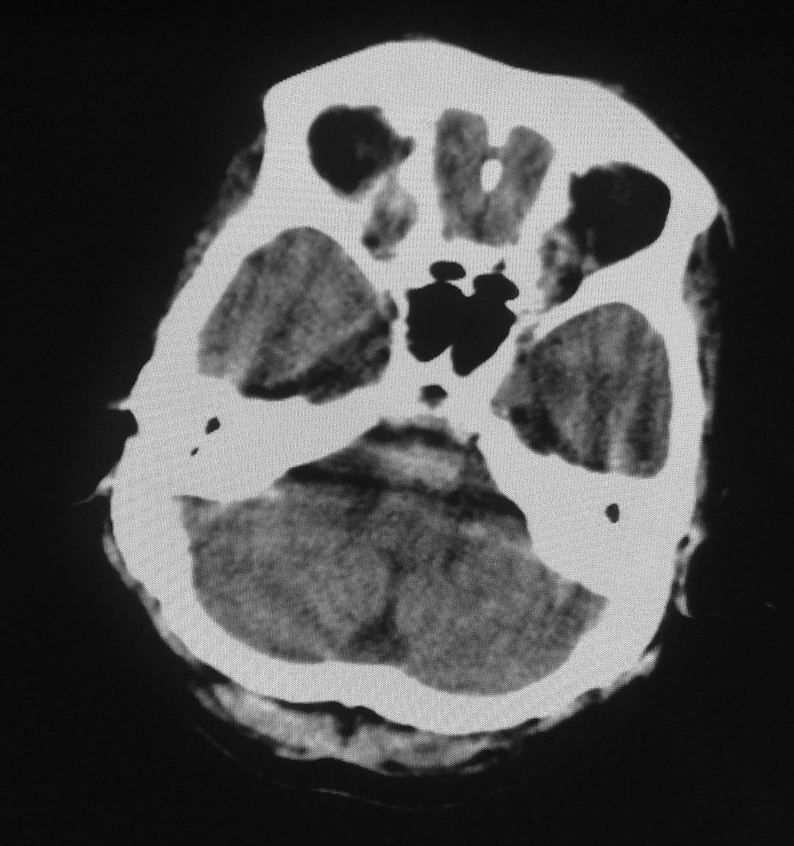

男,61岁,发热,有脑出血病史。

右侧基底节,放射冠软化灶,胼胝体发育不良 脑积水原因待查。

脑积水【脑室血块阻塞?】

脑积水!四脑室显示不清,导水管梗阻?建议mri!

右侧基底节及放射冠软化灶,脑积水,四脑室显示不清,导水管梗阻?建议mri!

梗阻性脑积水,出血后粘连所致

1)右侧基底节区、右侧放射冠及右侧丘脑软化灶。2)脑积水。